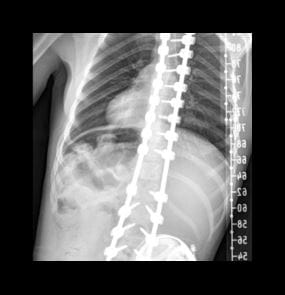

Paige’s spine before surgery

Paige Williams, 11, the second patient successfully treated at UH with FIREFLY®, had worn a brace or cast for most of her life due to congenital scoliosis (curvature of the spine) and other vertebrae abnormalities. In addition to limiting her ability to move and play, Paige’s crooked spine was also affecting her heart and lung function and contributing to possible hip dysplasia.

Christina Hardesty, MD, a pediatric orthopedic surgeon at UH Rainbow Babies & Children’s Hospital worked with FIREFLY® engineers to turn CT scans of the young patient's spine into an anatomically matched 3D-printed model, giving Dr. Hardesty a clear picture of the patient's spine to help her prepare for surgery.